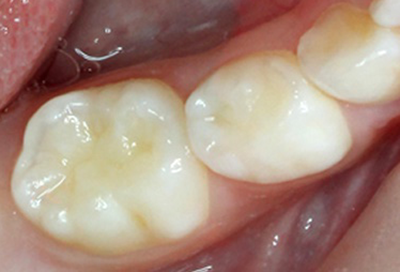

健康に見える乳歯

一見すると全く虫歯がないようにみえます。